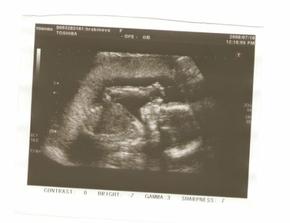

♥ 10.9. UZ ve 30.tt na Bulovce dopadl dobře. Mimoušek má 1384 gramů a odpovídá zhruba 30-31.týdnu těhotenství.